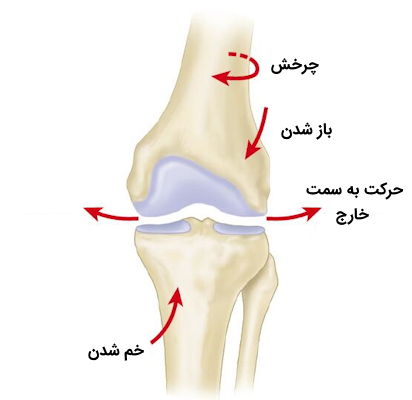

حرکات زانو

زانو یکی از مفصلهای لولایی بدن است که به طور عمده حرکات آن به صورت خم و باز شدن زانو در «سطح ساژیتال» (Sagittal Plane) قابل مشاهده میباشد، اما در دو حالت زیر امکان چرخش داخلی محدود این مفصل وجود دارد.

علاوه بر زمان خمیدگی زانو، امکان چرخش جانبی یا خارجی زانو در حین باز کردن آن نیز وجود دارد. در نتیجه باید گفت که مفصل زانو دارای چهار نوع حرکت است که به کمک ماهیچههای متفاوتی انجام میشود، در ادامه ماهیچههای مسئول هر حرکت را معرفی میکنیم.

- «باز شدن» (Extension): توسط «ماهیچه چهارسر ران» (Quadriceps Femoris) انجام میشود.

- «خم شدن» (Flexion): این حرکت توسط عضلات همسترینگ، گراسیلیس، سارتوریوس و پوپلیتئوس انجام میشود.

- «چرخش خارجی» (Lateral Rotation): ماهیچه دو سر رانی مسئول انجام این حرکت است.

- «چرخش داخلی» (Medial Rotation): پنج ماهیچه نیموتری، نیمغشایی، گراسیلیس، سارتوریوس و پوپلیتئوس مسئول این حرکت هستند.

با این توضیحاتی که ارائه شد متوجه میشویم که برخلاف مفصل آرنج، مفصل زانو را نمیتوان یک مفصل لولایی واقعی به حساب آورد؛ زیرا این مفصل دارای یک جزء چرخشی است که باعث میشود زانو در حین باز و بسته شدن حرکت خارجی نیز داشته باشد. در نتیجه این امر، زانو «مفصل لولایی تغییر یافته» (Modified Hinge Joint) به حساب میآید. میزان خم شدن زانو به دو نکته زیر بستگی دارد.

در حین باز شدن زانو، «کوندیلهای ران» (Femoral Condyles) بر روی صفحات بالایی استخوان درشت نی یا همان «پلاتوی تیبیا» (Tibial Plateaus) به سمت عقب هم میغلتند و هم میلغزند، دلیل این اتفاق نیز بزرگتر بودن نسبی سطح مفصلی پلاتوهای تیبیا است. این حرکت لغزشی رو به عقب از اهمیت بالایی برخوردار است؛ زیرا بدون آن، استخوان ران پیش از آن که فرآیند باز شدن کامل شود، از روی تیبیا یا درشت نی به سمت بیرون میلغزد.

حرکت اصلی مفصل پاتلوفمورال، لغزیدن سطح پشتی استخوان کشکک روی سطح کشککی استخوان ران است. لغزش این استخوان تا شکاف بین کوندیلی ادامه دارد. وظیفه اصلی کشکک این است که برای ماهیچه ران بازوی گشتاور بزرگتری ایجاد کند؛ بازوی گشتاور به فاصله بین محور ماهیچه و مرکز مفصل اشاره دارد، بنابراین کشکک باعث افزایش فاصله بین محور ماهیچه و مفصل میشود و به این ترتیب خاصیت مکانیکی ماهیچه افزایش پیدا میکند و «نیروی دورانی» (Angular Force) بهتری ایجاد میشود.